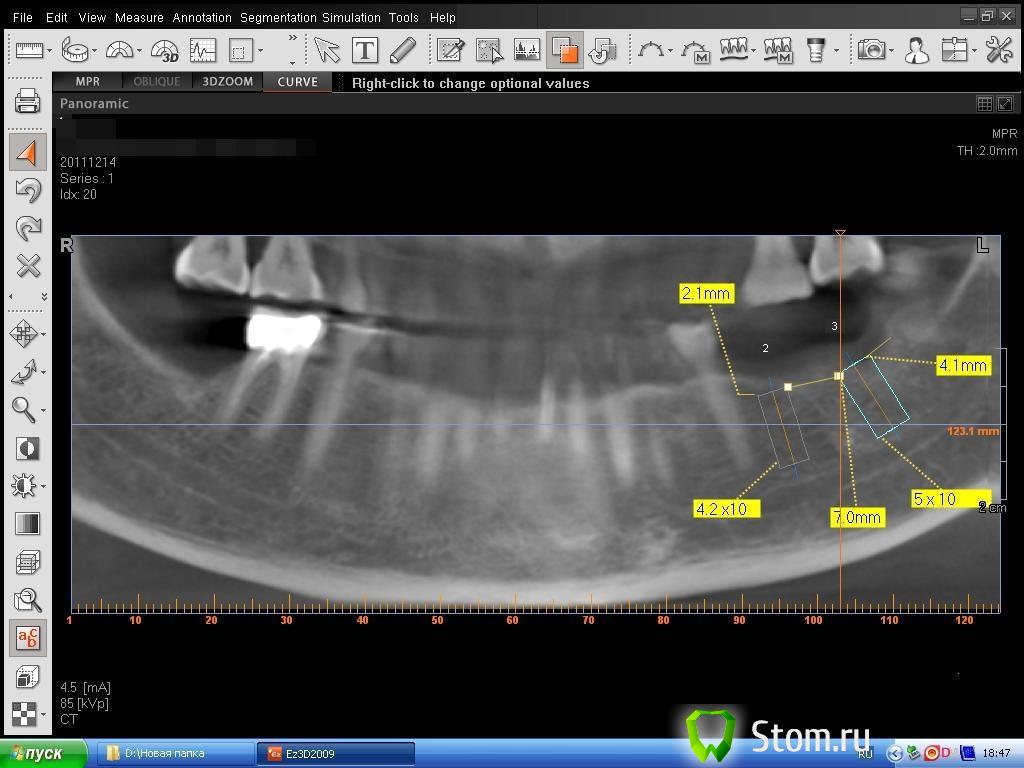

dent-a Опубликовано 21 декабря, 2011 Поделиться Опубликовано 21 декабря, 2011 Предыстория. КЛКТ на ватэке сделано в уважаемой фирме. Открыл, просчитал, получилось всё хорошо, сделал пару снэпов (фоток) рис 1. Дело было на работе вечером (windows xp). На следующий день то же самое (перепроверка) - но на домашнем компе (win 7) - открываю и результаты совсем иные рис 2 .... Сделал опять снэпшоты. Потом взял то - что просчитал днём ранее и экспортировал в планмековский считовод. Откалибровал в нём всё и .... всё оказалось верно рис 3. Где правда - то ?)) Позвонил в фирму....но там ко мне применили приём, как говорит один знакомый доцент, "мягкий посыл"... ну и на всякий им ещё в почту скинул. Раньше делал кт планмека в более дорогом месте...видимо и дальше буду делать дороже, т.к. таких аномалий не было. Поделитесь цифровым опытом. Может просто горе от ума :? Ссылка на комментарий